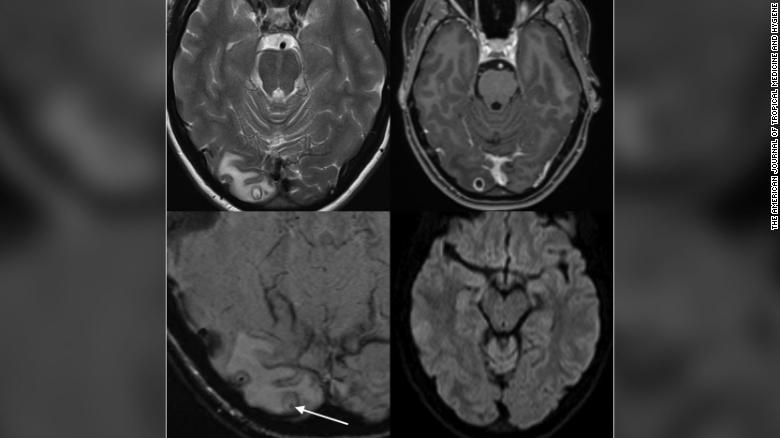

뇌에서 기생충이 발견된 A씨의 MRI 영상 [AJTMH 제공. 재판매 및 DB금지.]

뇌 자기공명영상(MRI)을 찍어본 연구진은 A씨의 뇌에서 종양이 아닌 물혹을 발견했다. 인간의 세포 조직으로 형성된 물혹이 아니라는 판단을 내린 연구진이 정밀 검사를 시행한 결과, 기생충들이 그 안에서 자라고 있었다는 사실을 확인했다.